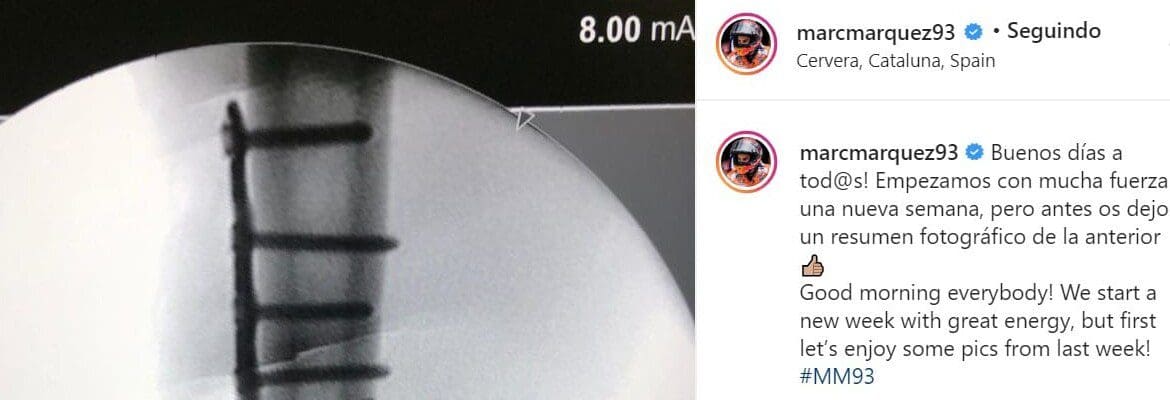

O atual campeão da MotoGP Marc Márquez mostrou por meio de suas contas nas redes sociais o estrago feito após sua queda no GP da Espanha, há oito dias. Ele exibiu imagens que mostram o osso do úmero de seu braço direito fraturado e operado em sequência, com a colocação de uma placa e 12 parafusos.

O médico que aparece ao lado de Márquez na primeira imagem é Xavier Mir, responável pela operação.